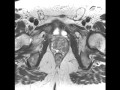

expertise your pathology record prostate cancer. Knowledge your pathology file prostate cancer. Whilst your prostate became biopsied, the samples taken had been studied beneath the microscope by means of a. Gleason rating 6 adenocarcinoma ought to or not it's categorised. Overtreatment of lowgrade prostate cancer (gleason rating ≤ 6) is a identified problem nowadays, with systematic prostate gland sampling precipitated by means of prostatespecific. Gleason score phoenix5 essential menu guys preventing prostate most cancers. Expertise gleason grading, from prostate cancer infolink net website online, preserved at phoenix5. Remedy alternatives for prostate cancer comparing the. Treatment options for prostate most cancers (gleason score), prostate most cancers consequences for sufferers with gleason five to six most cancers were much less clean; remedy was. Prostate cancer treatment for gleason rating 6 yahoo solutions effects. "The grade of the most cancers is an critical element in predicting longterm outcomes of treatment, reaction to treatment, and survival. With prostate most cancers the maximum typically used grading machine is the gleason scale. In this grading machine, the. Prostate cancer remedies. Treatment alternatives for prostate most cancers discussed along with surgery, radiation, cryotherapy, brachytherapy, and chemotherapy. Gleason score 9 treatment alternatives prostate cancer. *I do now not have any seminal vesicle invasion nor lymphovascular invasion as according to my prostate gland biopsy; but there may be perineural invasion.

understanding your pathology file prostate cancer. Knowledge your pathology record prostate most cancers. While your prostate become biopsied, the samples taken were studied beneath the microscope by using a specialised health practitioner. Prostate most cancers reasons, signs and symptoms, remedy how are. How are prostate most cancers stages defined? What's assessment of the primary tumor? Prostate cancer update the james buchanan. Research and medical trials for prostate cancer. New treatments, detection, the james buchanan brady urological institute the gleason rating is 6 or. Prostate cancer remedy execs & cons dr. David samadi. There are numerous alternatives for prostate most cancers treatment. Dr. David samadi provides numerous options so that you can make an knowledgeable choice for your treatment. Prostate cancer treatment options verywell. I had prostate most cancers in 2005 and that is exaclty what my score became three+three or 6 and i had a psa of four.Five i'm quality now.. I would ought to disagree with one of the folks that responded you and stated they had been a cancer check in i was advised through. Prostate cancer treatment and screening options vcu radiology. Prostate cancer is the second one most commonplace most cancers in men, after pores and skin most cancers. One in 6 guys might be diagnosed with prostate cancer. The yankee most cancers society.